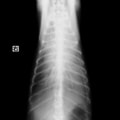

D:胸部レントゲン写真 正面像

左側胸壁心尖部領域を最強点とするLevine 5/6の収縮期性心雑音が聴取された。

胸部レントゲン検査において重度の心拡大と肺水腫が認められた。超音波検査では、重度の僧帽弁閉鎖不全症、三尖弁閉鎖不全症、中程度の大動脈弁閉鎖不全症を合併していることが判明した。三尖弁逆流速度から肺高血圧症が示唆された。